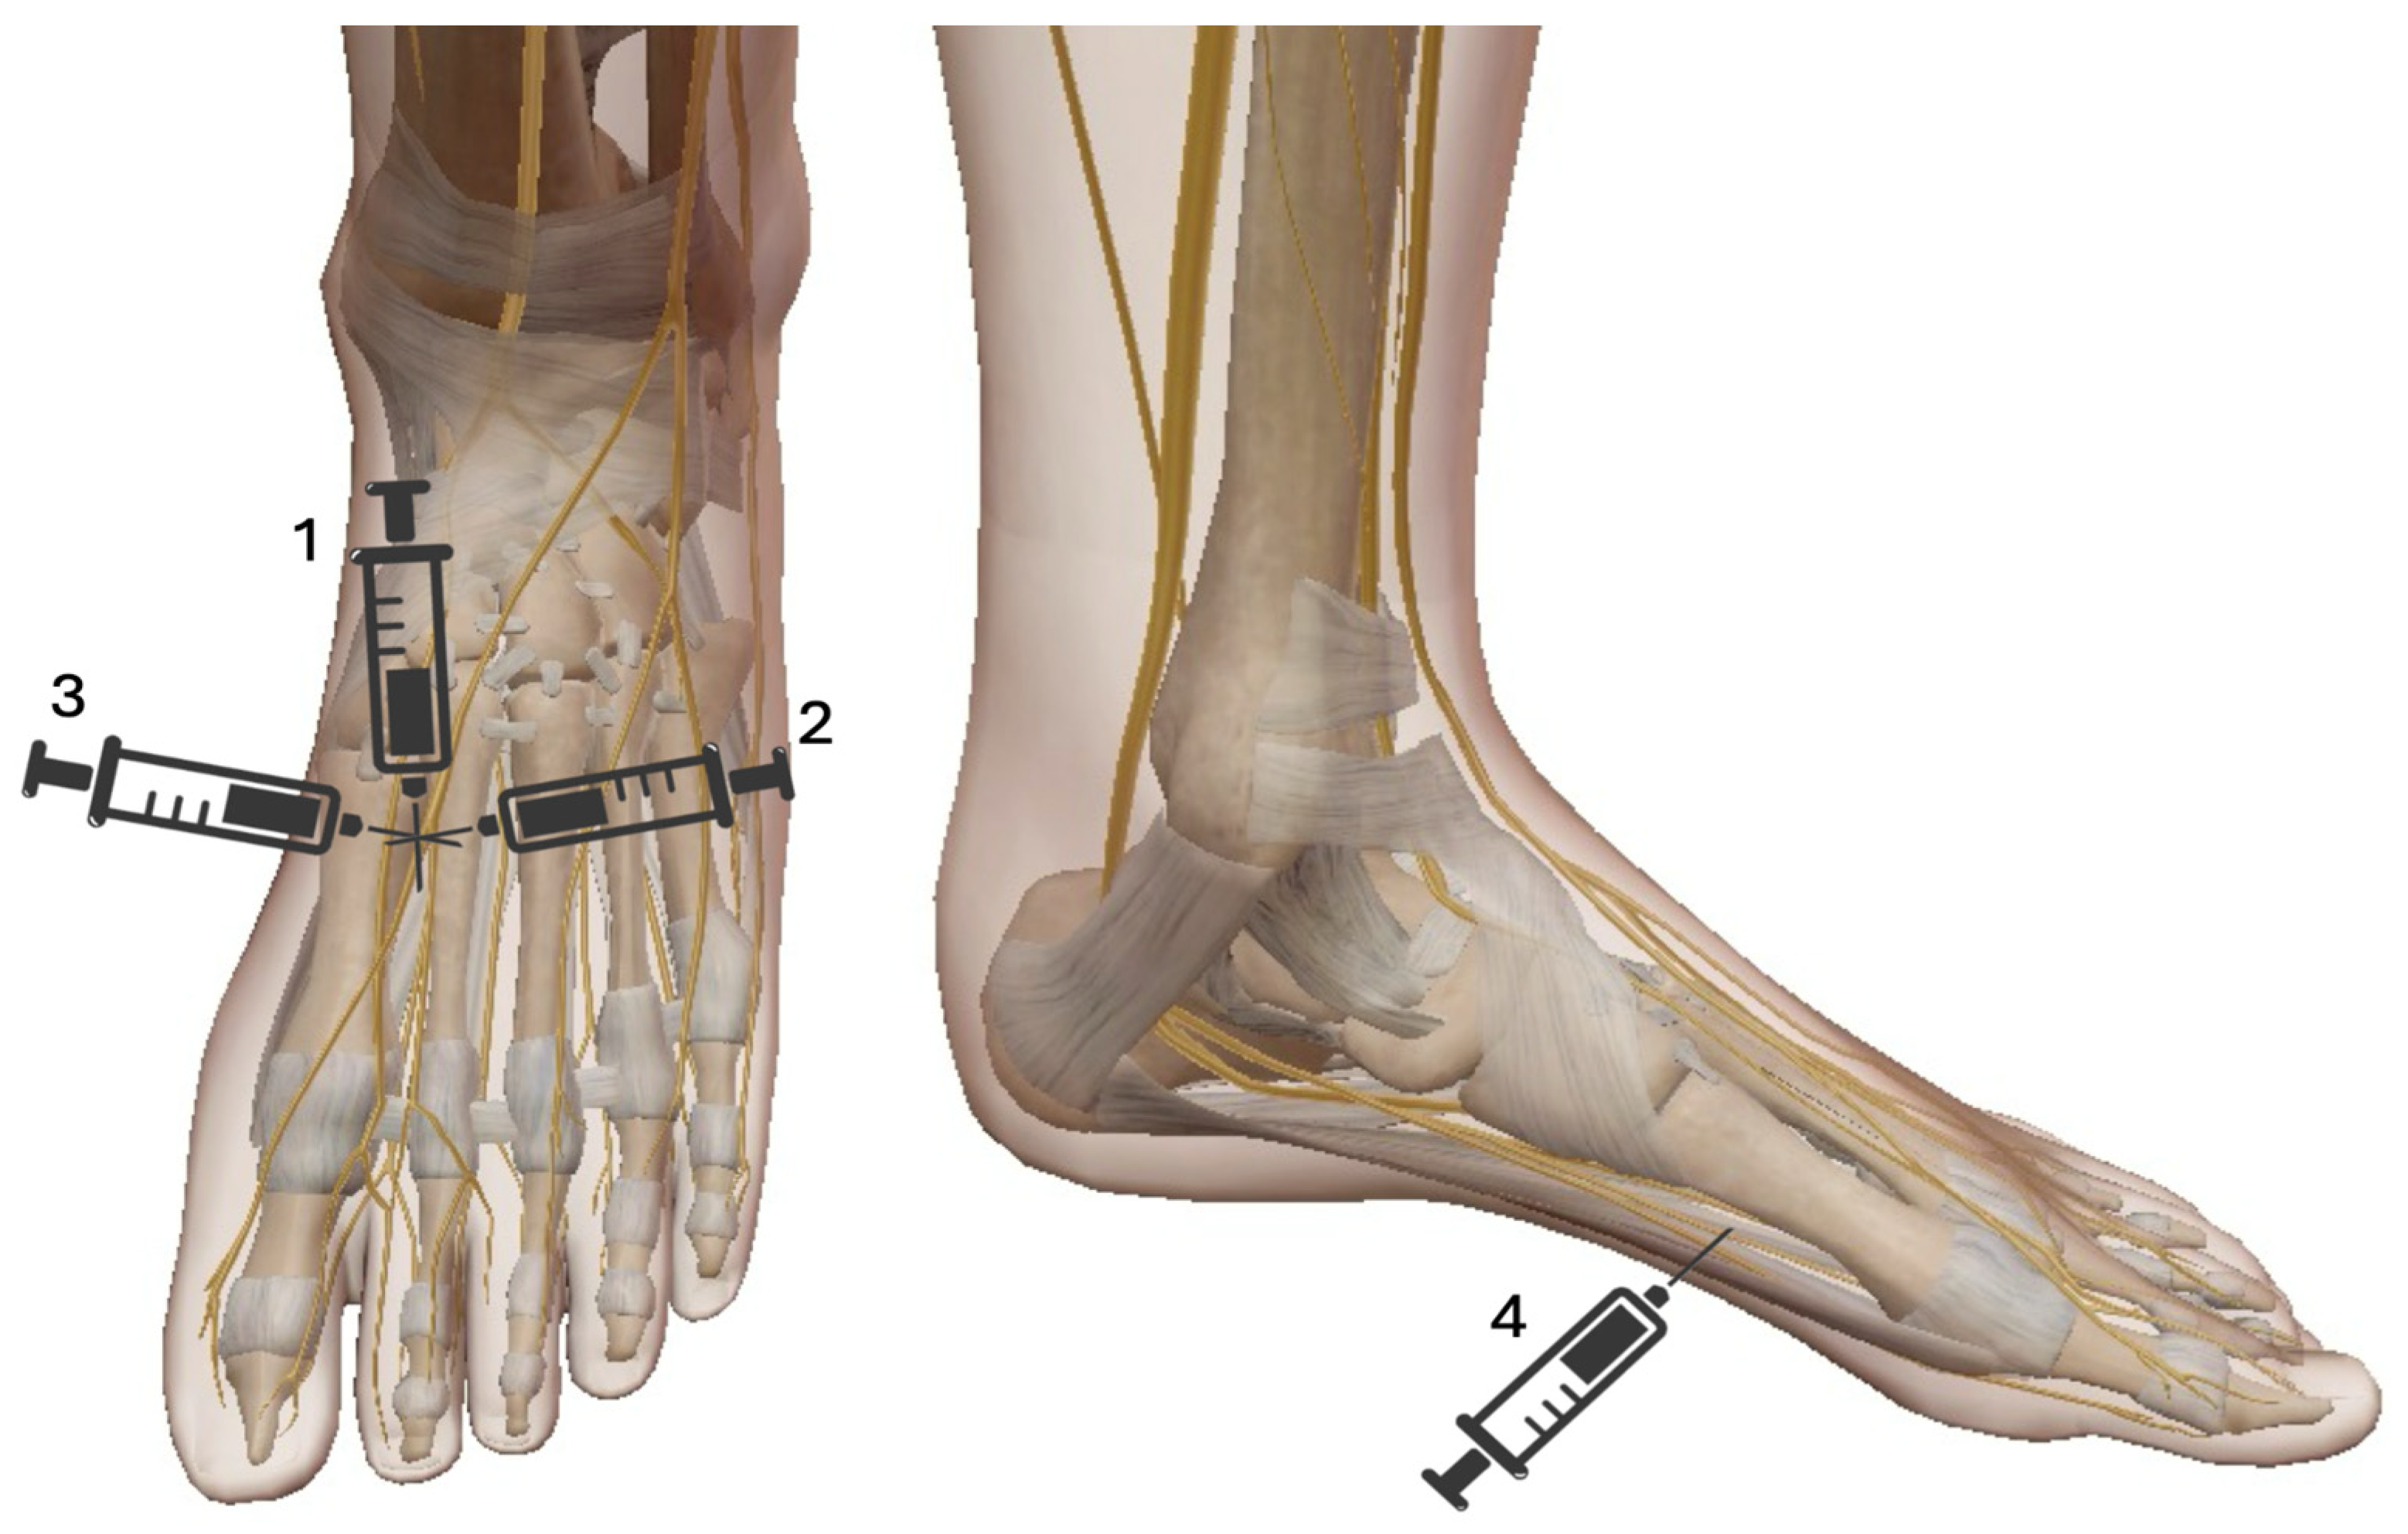

6. Mayo Block

The Mayo block is a regional anesthetic technique commonly used for hallux valgus surgery and first metatarsal procedures. It provides effective analgesia by blocking the terminal branches of the saphenous, deep peroneal, superficial peroneal, sural, and medial plantar nerves. The Mayo block is suitable for various surgical interventions, including bunionectomy, correction of hallux valgus and hallux rigidus, surgery for ingrown toenails, first metatarsal osteotomies, and other soft tissue procedures involving the great toe and medial foot. [36] This technique involves subcutaneous injection of a local anesthetic (typically lidocaine or bupivacaine) along a horseshoe-shaped line at the base of the first metatarsal (Figure 9). The required volume generally ranges from 10 to 15 mL, depending on patient anatomy and the desired duration of anesthesia. Careful aspiration before injection is essential to avoid inadvertent intravascular administration. The advantages of the Mayo block include effective perioperative and postoperative analgesia, a reduced need for general anesthesia or systemic opioids, facilitation of ambulatory surgery, and a lower risk of systemic side effects compared to general anesthesia. Although considered relatively safe, potential complications include hematoma formation due to accidental vascular puncture, transient nerve injury with paresthesia or dysesthesia, and local anesthetic systemic toxicity (LAST) if excessive doses or intravascular injection occur. Compared to direct infiltration, it requires less local anesthetic, respects tissue planes, and is associated with a very low failure rate, well below 1%. Its use can improve operating room efficiency and reduce the risks associated with general or major conduction anesthesia.

Figure 9. Mayo Block. The Mayo Block consists of 4 different injections each with 3–5 mL of local anesthetic (LA): 1. Insertion point proximally and dorsally within the first intermetatarsal space, followed by advancing the needle in a plantar direction while administering (LA); 2. The needle is then partially withdrawn and redirected medially to create a subcutaneous wheal along this path with an additional injection of LA; 3. the needle is reinserted laterally to raise another subcutaneous wheal with LA along its trajectory; 4. The needle is withdrawn again and advanced plantar-medially beneath the metatarsal bone to deliver of LA from the medial to the lateral aspect.